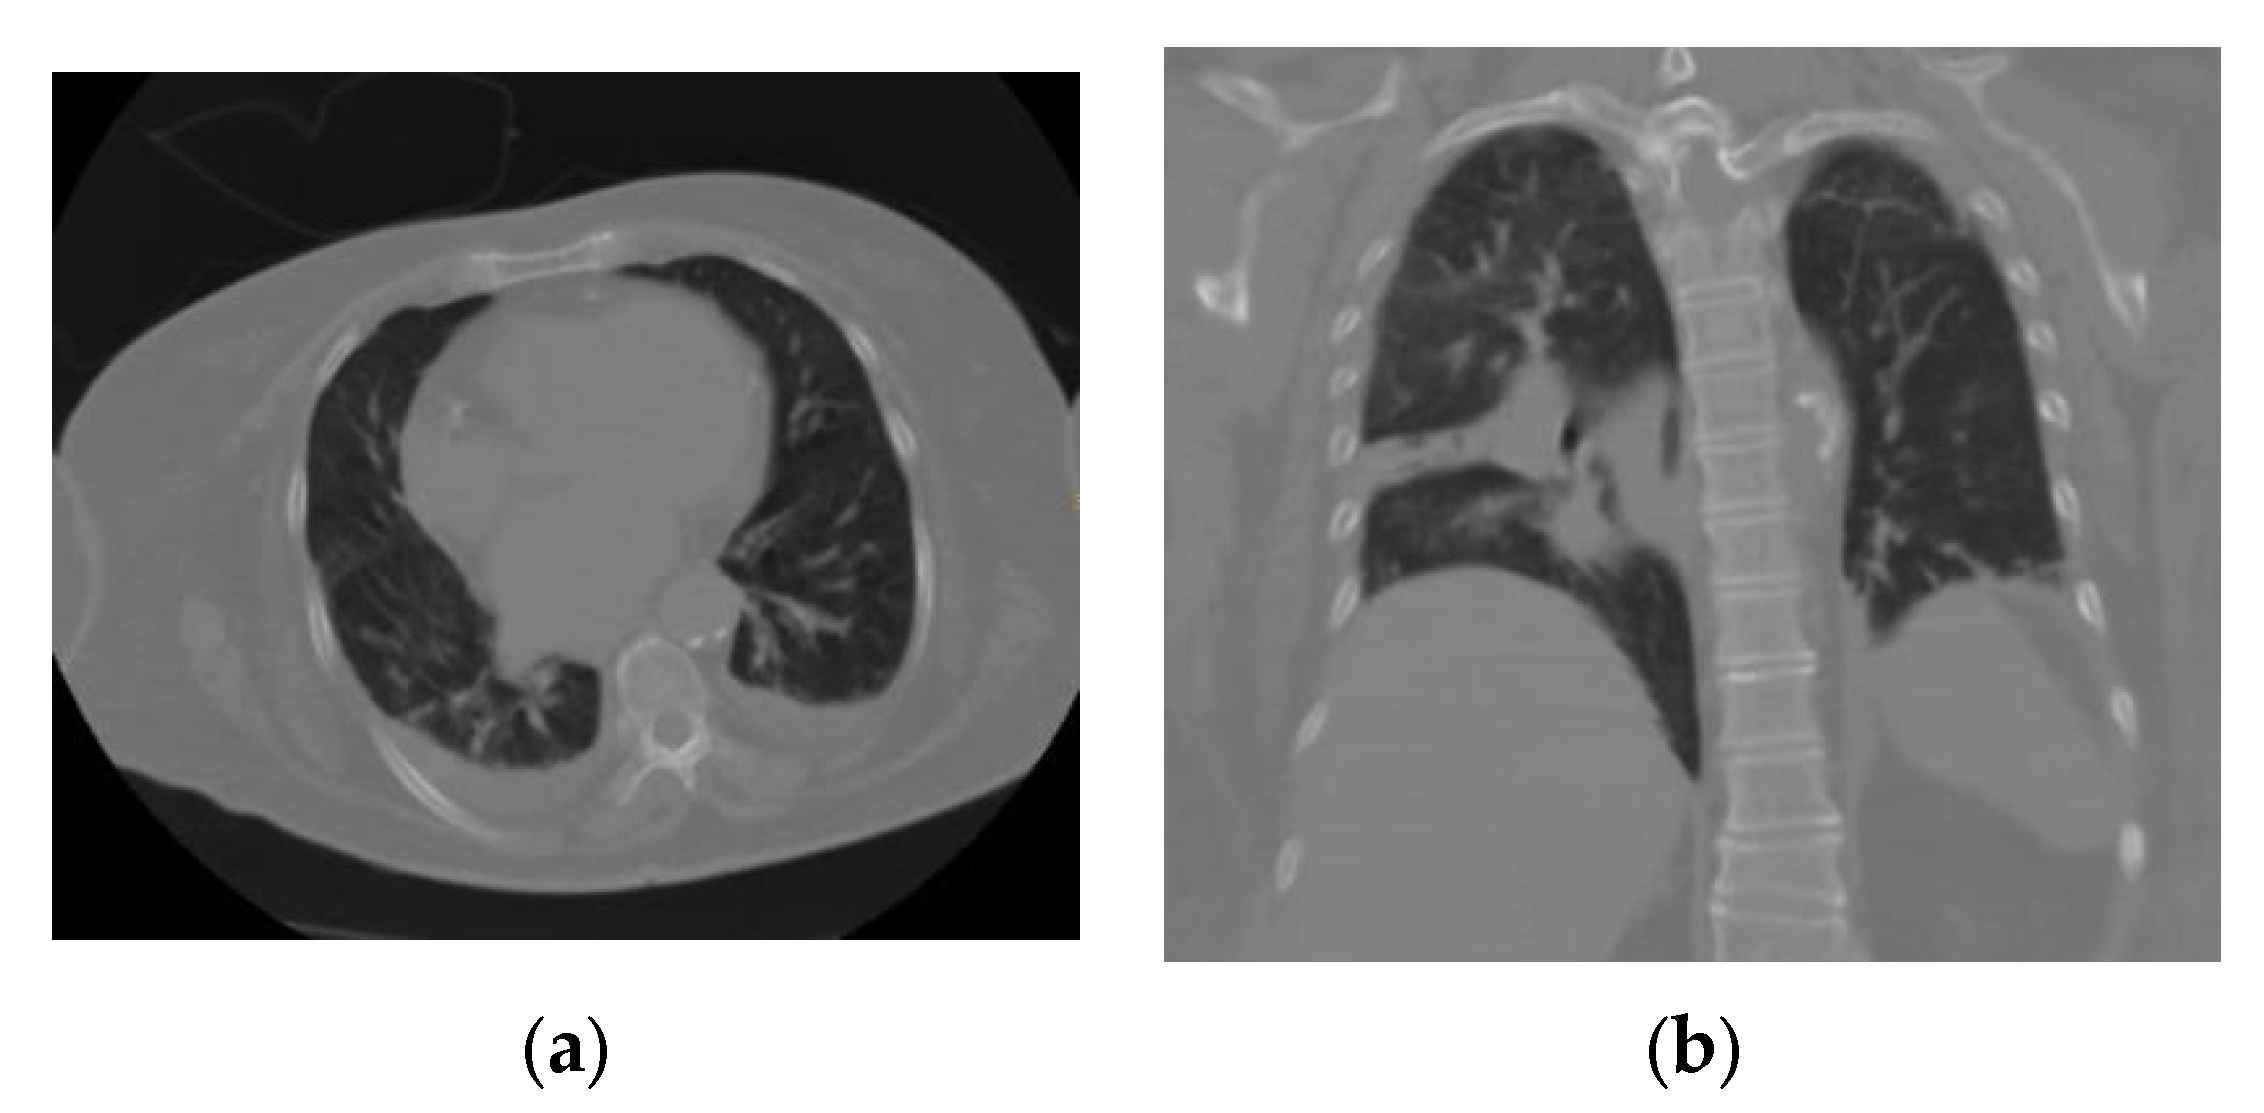

CO-RADS 3: a study with uncertain or indeterminate findings that shows areas suggestive of COVID-19, but also of other pathologies (Figure 3).

(a) Axial section and (b) coronal section of a patient with an indeterminate interstitial opacity pattern that, being unique, septal, and lobular with associated pleural effusion, did not allow confirmation or rule out an association with COVID-19; these findings may be associated with any viral pneumonia (in this case, the patient had a negative RT–PCR test result for SARS-CoV-2).